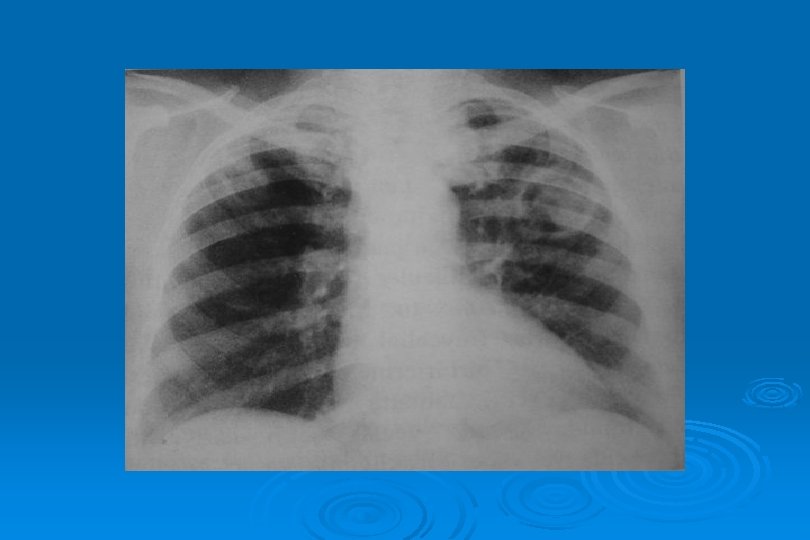

İnfluenza Virüs Pnömonisi

VİRAL AC ENFEKSİYONLARI Toplum kökenli pnömonilerin % 25’i Ø Yaygın ya da dağınık infiltrasyon şeklinde olan bakteriyel pnömonilerden ayrımı çok zordur Ø Klinik bilgi verilmediğinde olgularda pnömoninin viral veya bakteriyel olduğunu tahmin etmek güçtür Ø Lober genişleme, mikroabseler, kavitasyon ve ampiyem bakteriyel pnömoniyi destekler Ø

VİRAL AC ENFEKSİYONLARI Ø Viral pnömoni damlacık enfeksiyonudur Ø Trakeit, bronşit ve bronşiolit tablosu ortaya çıkar Ø AC grafisinde hilustan perifere yayılım, asiner gölgeler ve yer peribronşial kalınlaşmalar saptanır

LOKALİZE VEYA YAYGIN HEMORAJİK ÖDEM Lokal olduğunda radyolojik görünümü segmenter veya lober pnömoniye benzer Ø Yaygın hemorajik ödem akut ve şiddetli viral pnömonide hızla ortaya çıkan bir tablodur Ø Perihiller perifere doğru azalan yaygın alveoler opasiteler görülür Ø Bazen plevral effüzyon olaya eşlik eder Ø İnfluenza virüsü en sık nedendir Ø